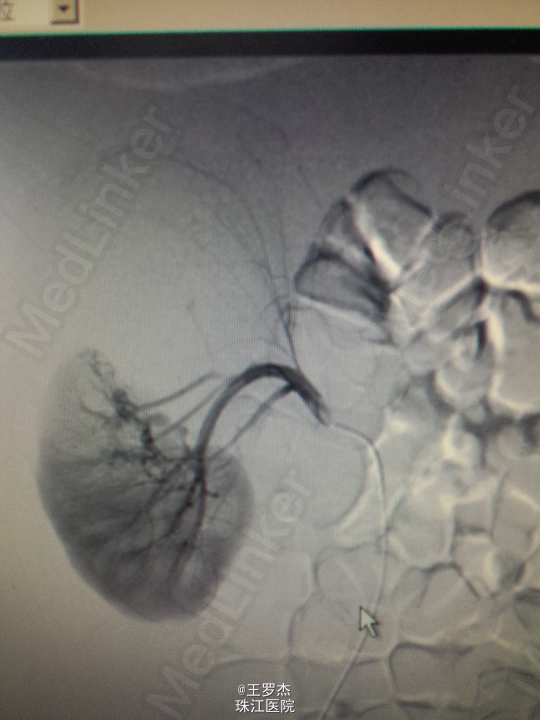

诊断治疗:右肾挫裂伤,保守治疗。3天后复查Hb89g/L,RBC2.65;复查CT提示包膜下及盆腔积血较前增多。请介入科会诊,行右肾动脉选择性栓塞。 介入:右肾挫裂伤,并上极动脉破裂出血及远端多处动静脉瘘形成,成功行超选择性病变血管栓塞术。